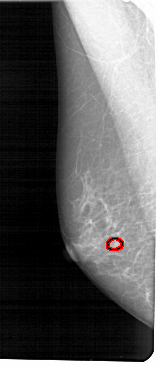

A_1545_1.RIGHT_MLO

RIGHT_MLO LINES 5221 PIXELS_PER_LINE 2416 BITS_PER_PIXEL 12 RESOLUTION 43.5 NON_OVERLAY

FILE: A_1545_1.LEFT_MLO.OVERLAY

TOTAL_ABNORMALITIES 1

ABNORMALITY 1

LESION_TYPE MASS SHAPE LOBULATED MARGINS OBSCURED

ASSESSMENT 4

SUBTLETY 2

PATHOLOGY BENIGN

TOTAL_OUTLINES 1